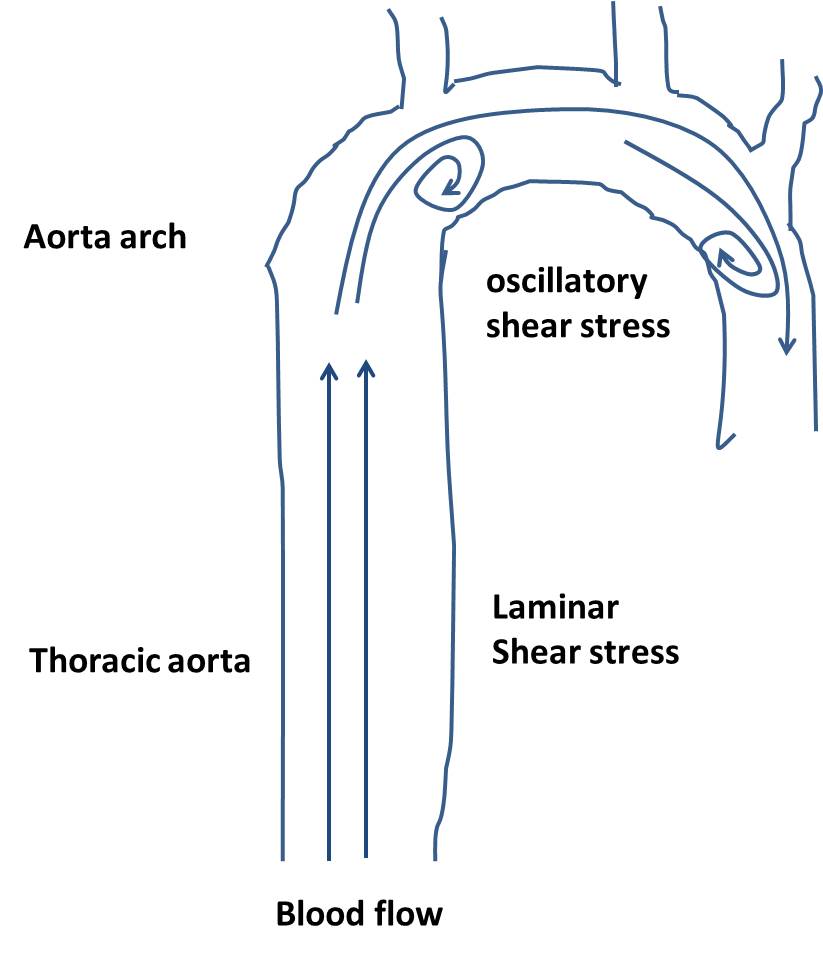

Atherosclerotic plaques occur at sites of low/disturbed blood flow …

| Hemodynamic forces exerted on the arteries. (A) Trans-mural pressure …

Functional Roles of Shear Stress in Vascular Endothelial Cells